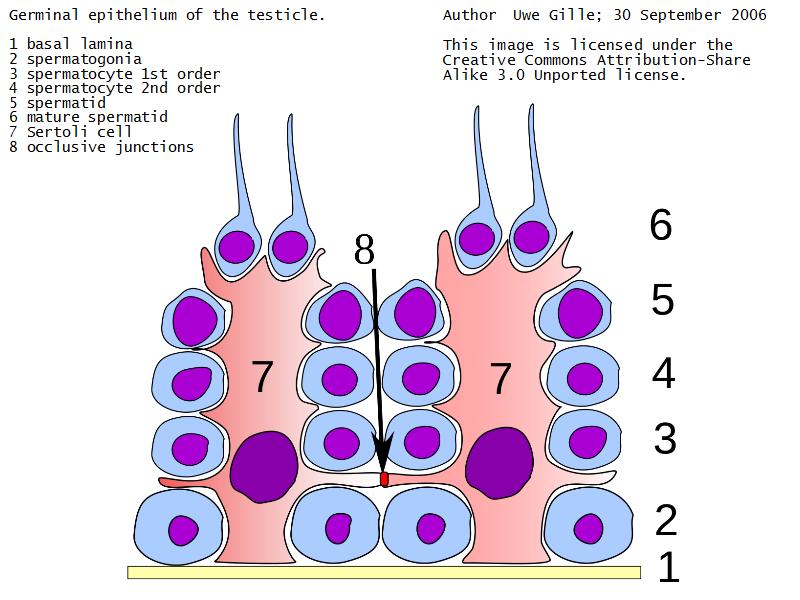

Sertoli cells

- Complex columnar shape

- Basal lamina to lumen

- Irregular outline

- Envelope developing germ cells

- Large pale nucleus with indentations & large nucleolus

- Occludens junctions with adjacent cells

- Establish blood-testis barrier

Spermatogenic cells

- Several stages of spermatogenesis

- Spermatogonia

- Primary spermatocytes

- Secondary spermatocytes

- Spermatids

- Spermatozoa

Spermatogonia

- Diploid

- Sits on basal lamina

- 3 types

- Pale type A

- Small, pale nucleus

- Produce pale type A or type B

- Dark type A

- Dark nucleus

- Reserve cell to produce pale type A

- Type B

- Undergo mitosis

- Form primary spermatocytes